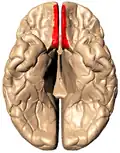

Анимированное изображение, прямая извилина отмечена красным